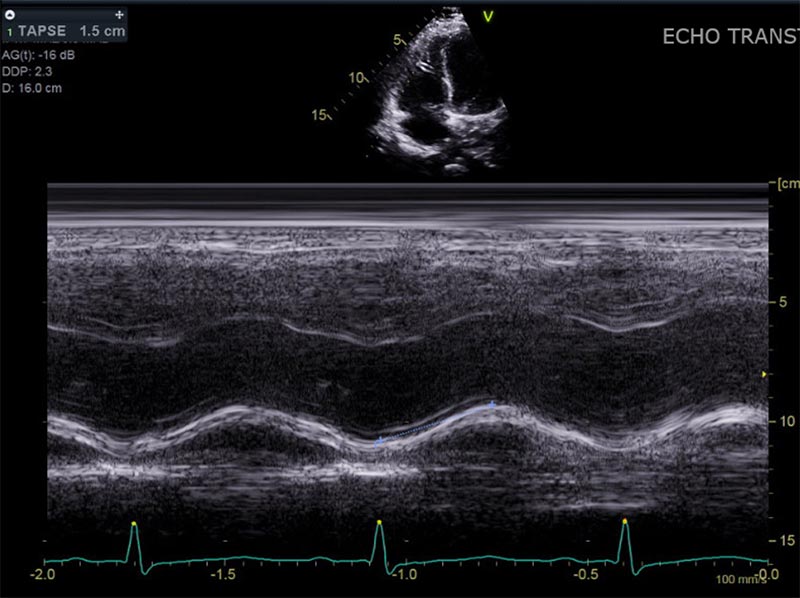

RV Strain

Description Here.